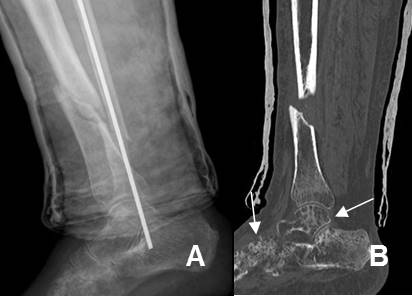

Fig 124. Seudoartrosis del escafoides.

A: Rx AP y B: TAC reconstrucción coronal. Seudoartrosis del escafoides, manejada con tornillo.